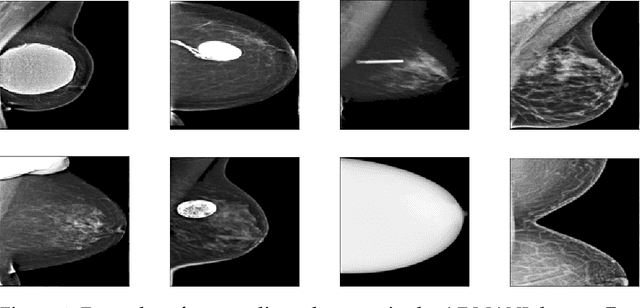

Abstract:The ADMANI datasets (annotated digital mammograms and associated non-image datasets) from the Transforming Breast Cancer Screening with AI programme (BRAIx) run by BreastScreen Victoria in Australia are multi-centre, large scale, clinically curated, real-world databases. The datasets are expected to aid in the development of clinically relevant Artificial Intelligence (AI) algorithms for breast cancer detection, early diagnosis, and other applications. To ensure high data quality, technical outliers must be removed before any downstream algorithm development. As a first step, we randomly select 30,000 individual mammograms and use Convolutional Variational Autoencoder (CVAE), a deep generative neural network, to detect outliers. CVAE is expected to detect all sorts of outliers, although its detection performance differs among different types of outliers. Traditional image processing techniques such as erosion and pectoral muscle analysis can compensate for the poor performance of CVAE in certain outlier types. We identify seven types of technical outliers: implant, pacemaker, cardiac loop recorder, improper radiography, atypical lesion/calcification, incorrect exposure parameter and improper placement. The outlier recall rate for the test set is 61% if CVAE, erosion and pectoral muscle analysis each select the top 1% images ranked in ascending or descending order according to image outlier score under each detection method, and 83% if each selects the top 5% images. This study offers an overview of technical outliers in the ADMANI dataset and suggests future directions to improve outlier detection effectiveness.